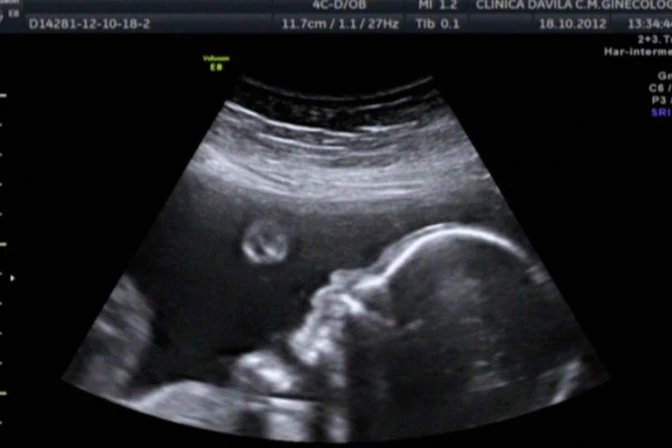

Un reciente estudio realizado por la Universidad de Lancaster, en Reino Unido, reveló que los bebés pueden reconocer los rostros cuando aún están en el vientre de sus madres.

Los científicos hicieron el experimento con 39 bebés no nacidos que estaban en el tercer trimestre de gestación utilizando la tecnología ultrasonido 4D.